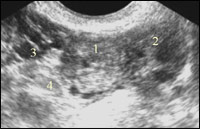

При нарушенной трубной беременности в проекции маточной трубы обнаруживается образование с нечеткими, неровными контурами и гетерогенной, кистозно-солидной структуры, часто в общем конгломерате с яичником.

Трубная беременность, особенно прервавшаяся, в 60 % случаев приводит к появлению свободной жидкости в малом тазу, а при кровотечении свыше 300-400 мл позволяет констатировать не только трубы, но и связочный аппарат матки и яичников. Геморрагическая жидкость при ультразвуковом исследовании имеет рассеянные эхогенные включения различного размера, а сгустки крови визуализируются как образования неправильной формы и повышенной эхогенности. Однако необходимо учитывать возможность скопления жидкости в околоматочном пространстве в результате других патологических или физиологических процессов (экссудат при воспалении внутренних половых органов или апоплексии кист яичников, а также овуляторная жидкость). Этот эхографический признак имеет значение только в сочетании с другими ультразвуковыми признаками внематочной беременности.

Нарушения развития трубной беременности может влиять на изображение срединного комплекса матки. При неразвивающейся или прервавшейся беременности в 10-61 % случаев имеется расширение полости матки за счет гематометры и фрагментов гравидарного эндометрия.